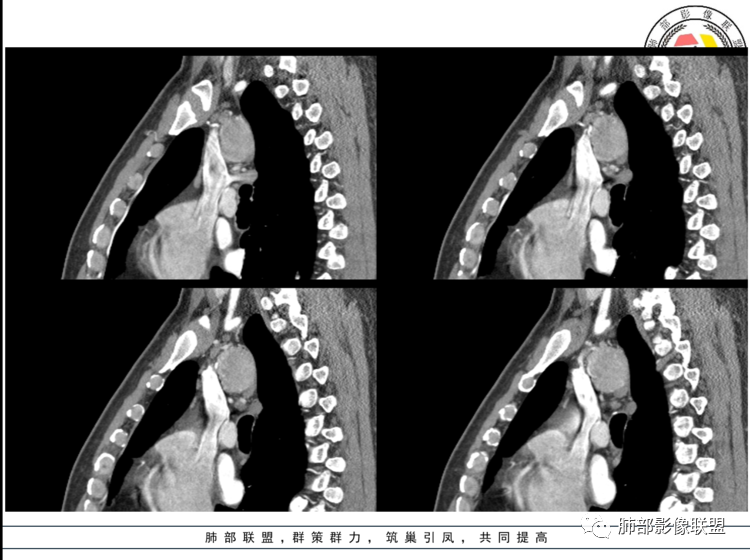

3.1单发型CD的肺部表现

单发型CD多为透明血管型,所以明显强化和中央分枝状钙化具有特征性。在CT上表现圆形或类圆形软组织密度影,伴或不伴周围淋巴结增生,体积一般较大,边缘光整,病灶中央的弧形、线样、分枝样及枯枝样钙化(因为肿块内增生的血管组织玻璃样变或退变后钙盐沉积,故多呈血管样铸型的分支状或枯枝状);透明血管型因为其内血供丰富,周围可见粗大的供血动脉,在多期扫描动脉早期明显强化,强化程度与大血管相仿,又由于病灶内血管壁玻璃样变或纤维化及内皮细胞过度增生致血管腔狭窄,对比剂退出减慢,故延迟扫描扫描仍可持续强化,呈“早进晚出”的强化方式。因为其血供丰富,坏死、囊变或出血少见,但是有时候病灶内灶状或条片状低密度影,是纤维组织或发生玻璃样变性的血管结构,而不是缺血坏死区。

中年男性,上纵隔气管旁软组织肿块,边界清楚,与周围结构脂肪间隙存在,长轴与气管一致,增强明显不均匀强化,静脉期及延迟期强化稍减退。强化明显的纵隔肿瘤,考虑CD,鉴别副神经节瘤。淋巴瘤强化不符合,神经鞘瘤没看到明显的A区、B区,暂不考虑。

定位,中纵隔,上腔静脉向前推移。椭圆形软组织影,边界清晰,密度均匀,周围脂肪间隙清晰。增强明显均匀强化。

考虑,良性,CD,鉴别副节瘤。